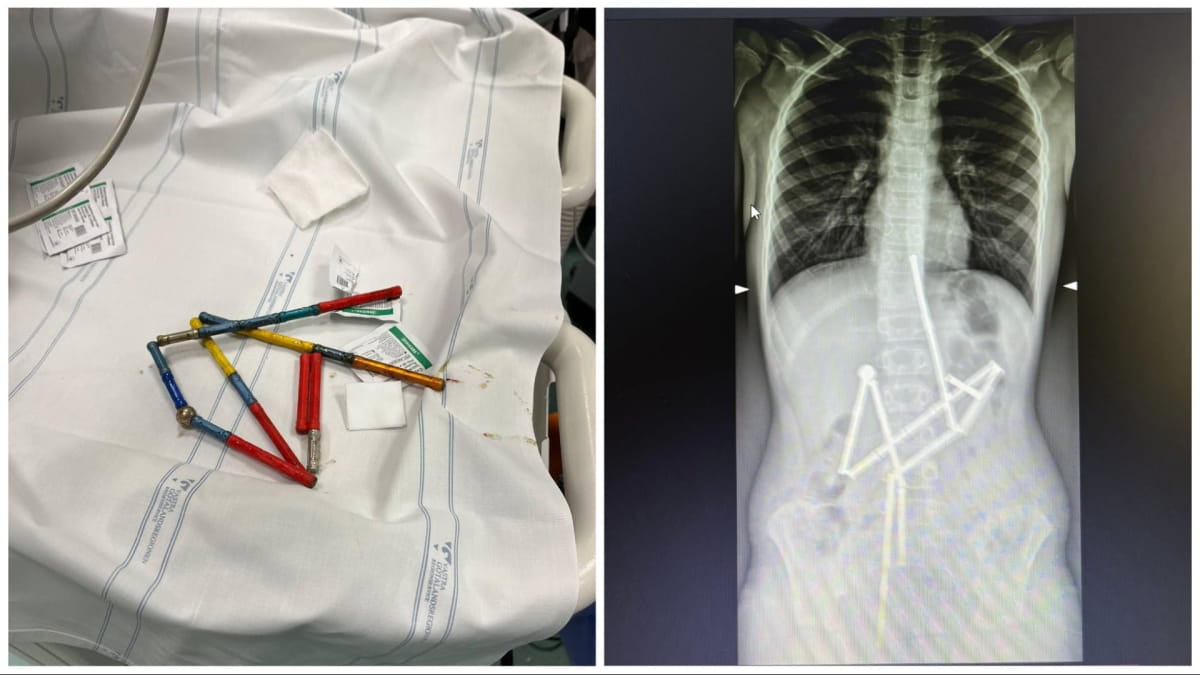

Лікарі НДСЛ "Охматдит" успішно врятували маленького хлопчика, який випадково проковтнув 20 магнітів з іграшкового конструктора. Про це повідомляє "Дивогляд" із посиланням на Facebook-сторінку НДСЛ "Охматдит".

Батьки хлопчика звернулися за допомогою до медичного закладу, коли виявили, що він скаржиться на біль у животі. Лікарі екстреної допомоги відразу провели огляд та зібрали анамнез, а потім вирішили направити хлопчика на додаткове обстеження.

Перший рентген показав наявність групи сторонніх тіл у травному тракті дитини. Виявилося, що це магнітний конструктор, складений з 20 магнітів, розташованих у різних частинах шлунково-кишкового тракту, але вони були з'єднані між собою.

Медичний консиліум прийняв рішення про негайну операцію, адже кожна година затримки могла загострити стан малюка.

"Відмінність магнітів від інших сторонніх тіл, які можуть проковтнути діти, полягає у їх притягненні один до одного та защемленні тканин. Як наслідок, виникають зони некрозу (змертвіння), перфорації порожнистих органів, шлунково-кишкові непрохідності тощо", – розповіли медики.

Під час операції лікарям вдалося видалити перший магніт разом з ланцюжком з 18 елементів конструктора. Однак один магніт залишився, тому хірурги здійснили лапаротомію для його вилучення. Під час операції було виявлено п'ять перфорацій та останній елемент конструктора, і всі ці дефекти були усунені, а магніт видалено.